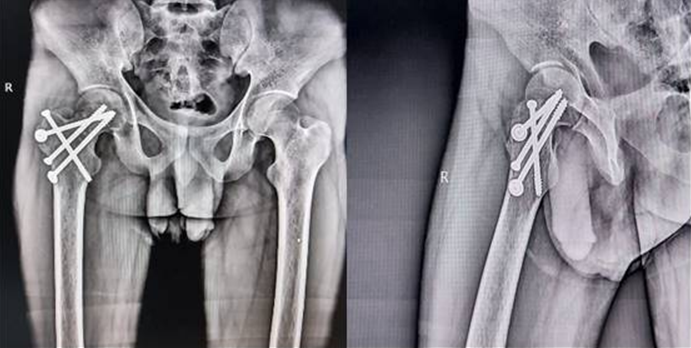

Figure 4- : 18 months post post-operative anteroposterior AP and lateral X-rays.

At 4 months post-operative, the patient had achieved an excellent, painless range of motion of the affected hip, allowing him to resume his job. At the latest follow-up at 18 months, there was no radiological evidence of AVN (Fig. 5).